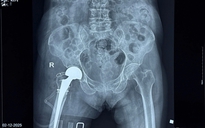

Cảm xúc của những bệnh nhân thoát cảnh ngồi xe lăn sau khi thay khớp háng

ẢNH: T.T

Từ ngày 10 - 14.4.2026, Viện Chấn thương Chỉnh hình, Bệnh viện Quân y 175 phối hợp cùng OWC đã thực hiện phẫu thuật thay khớp háng nhân tạo miễn phí cho 37 bệnh nhân. Các bệnh lý chủ yếu bao gồm hoại tử chỏm xương đùi, thoái hóa khớp háng... những nguyên nhân gây suy giảm nghiêm trọng khả năng vận động. Mỗi ca phẫu thuật được tài trợ hoàn toàn.

"Sau nhiều năm đau đớn, tôi chưa từng nghĩ mình có thể đi lại bình thường như hôm nay. Gia đình khó khăn nên việc mổ là điều rất xa vời. Tôi thật sự biết ơn các bác sĩ và chương trình đã cho tôi cơ hội được đi lại một lần nữa", cô Ngọc Ảnh (ở TP.HCM) khớp háng nhân tạo bên phải năm 2023 bày tỏ.